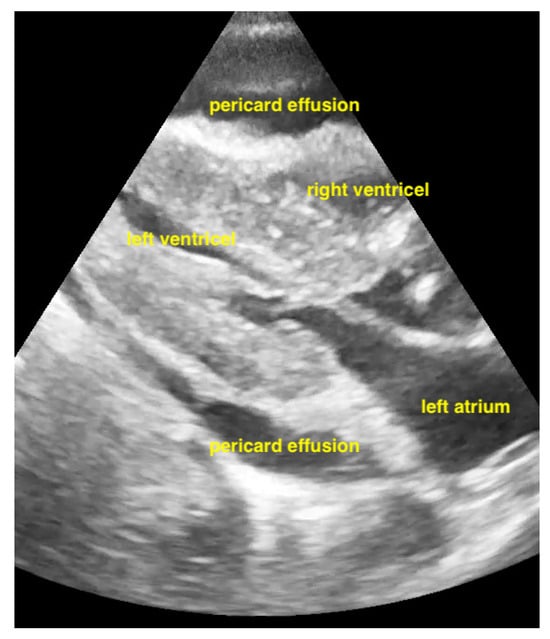

Pericardial effusions are best identified with a convex or sector probe in the subxiphoid or parasternal view. While it is important to simply note whether an effusion is present, sonographic and clinical (hypotension and tachycardia) evidence of cardiac tamponade should be sought. These include diastolic collapse of the right atrium free wall, followed by free wall collapse of the right ventricle as tamponade worsens. Both the apical and subcostal four-chamber views are ideal for this assessment. However, the subcostal window allows for a rapid transition to the proximal IVC view, which is dilated (>2 cm) and does not vary with respiration in cases of cardiac tamponade. Although many cases of medium and large pericardial effusions are obvious on ultrasound, there are notable exceptions. These include some hemorrhagic effusions which show significant coagulation, thus appearing echogenic on ultrasound, leading to frequent confusion with an epicardial fat pad or even a portion of the myocardial wall. Conversely, some epicardial fat pads may be confused with pericardial effusions, especially by novices. Differentiating between the two is easy by using anatomical knowledge. An epicardial fat pad does not extend enough inferiorly to be seen on a longitudinal IVC inlet view, while a pericardial effusion will in virtually all cases (Figure 7, Figure 8, Figure 9 and Figure 10).

Pericardial effusion in subxiphoidal view.

Figure 9.

Pericardial effusion in apical four chamber view compresses the right atrium slightly (RA = right atrium, LA = left atrium, RV = right ventricle, LV = left ventricle).

Figure 10.

Pericardial effusion in subxiphoidal view compresses the right ventricle.